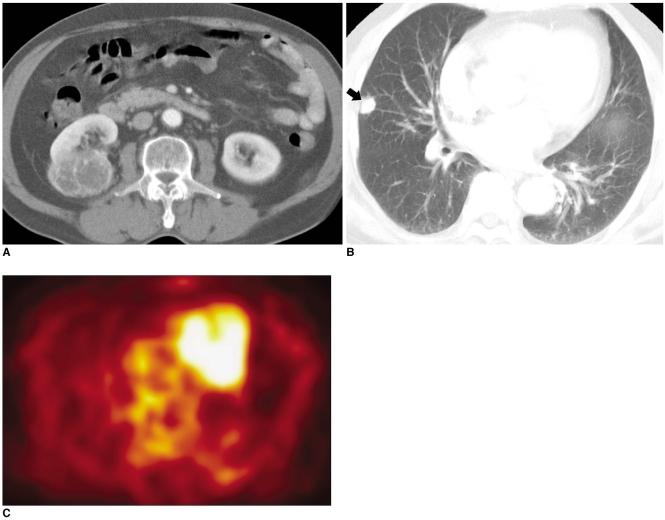

Fluorodeoxyglucose (FDG)-positron emission tomography (PET) is being used more and more to differentiate benign from malignant focal lesions and it has been shown to be more efficacious than conventional chest computed tomography (CT). However, FDG is not a cancer-specific agent, and false positive findings in benign diseases have been reported. Infectious diseases (mycobacterial, fungal, bacterial infection), sarcoidosis, radiation pneumonitis and post-operative surgical conditions have shown intense uptake on PET scan. On the other hand, tumors with low glycolytic activity such as adenomas, bronchioloalveolar carcinomas, carcinoid tumors, low grade lymphomas and small sized tumors have revealed false negative findings on PET scan. Furthermore, in diseases located near the physiologic uptake sites (heart, bladder, kidney, and liver), FDG-PET should be complemented with other imaging modalities to confirm results and to minimize false negative findings. Familiarity with these false positive and negative findings will help radiologists interpret PET scans more accurately and also will help to determine the significance of the findings. In this review, we illustrate false positive and negative findings of PET scan in a variety of diseases.